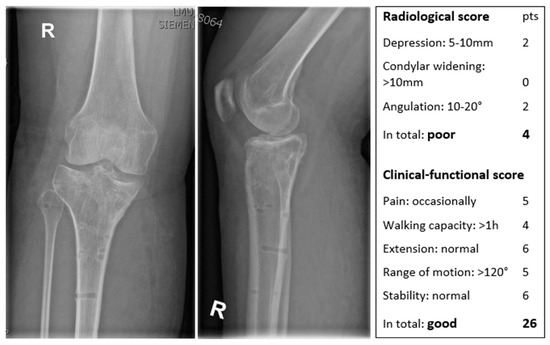

2.7. Rasmussen Scores

| Radiological Score | Pts | Clinical–Functional Score | Pts | ||

|---|---|---|---|---|---|

| Depression | None | 6 | Pain | No pain | 6 |

| <5 mm | 4 | Occasional pain | 5 | ||

| 5–10 mm | 2 | Stabbing pain in certain positions | 4 | ||

| >10 mm | 0 | Constant pain after activity | 2 | ||

| Condylar widening | None | 6 | Significant rest pain | 0 | |

| <5 mm | 4 | Walking capacity | Normal for age | 6 | |

| 5–10 mm | 2 | Outdoor > 1 h | 4 | ||

| >10 mm | 0 | Outdoor > 15 min | 2 | ||

| Angulation (varus/valgus) | None | 6 | Only indoors | 1 | |

| <10° | 4 | Immobile | 0 | ||

| 10–20° | 2 | Extension | Normal | 6 | |

| >20° | 0 | Lack of extension < 10° | 4 | ||

| Lack of extension > 10° | 2 | ||||

| Range of motion | >140° | 6 | |||

| >120° | 5 | ||||

| >90° | 4 | ||||

| >60° | 2 | ||||

| >30° | 1 | ||||

| >0° | 0 | ||||

| Stability | Normal stability | 6 | |||

| Instability in 20° flexion | 5 | ||||

| Instability in extension <10° | 4 | ||||

| Instability in extension >10° | 2 | ||||

| Radiological Score | Clinical–Functional Score | Evaluation | |||

| 18 points | 27–30 points | excellent | |||

| 12–17 | 20–26 | good | |||

| 6–11 | 10–19 | fair | |||

| 0–5 | 4–9 | poor | |||